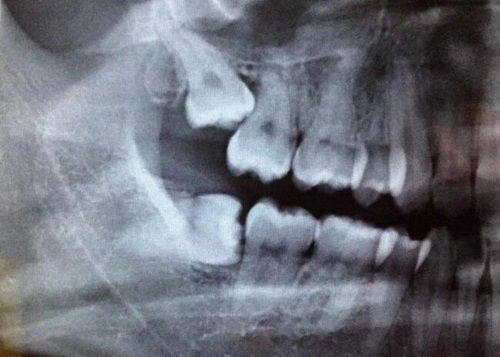

根管治疗又称牙髓治疗,简单来说就是针对已经感染或坏死的牙髓组织进行的专精口腔治疗。我们的牙齿内部并非实心结构,而是存在一个包含牙髓(牙神经、血管和结缔组织)的根管系统,当细菌侵入牙髓、引发牙髓炎或根尖周炎时,牙髓会出现坏死、感染,此时如果不及时处理,感染会进一步扩散到根尖周组织,导致牙龈肿胀、牙齿松动甚至脱落。根管治疗的核心操作就是通过清除根管内的感染或坏死牙髓,对根管进行冲洗消毒后严密填充,再封闭牙冠部,以此去除根管内感染物对根尖周围组织的刺激,防止根尖周病变发生或促进其愈合,更终保留患牙,避免直接拔牙。

根管治疗通常需要2-4次就诊,相邻两次间隔1-2周,让根管内药物充分发挥作用、炎症消退,整个流程分为5个关键步骤:第一步是开髓清理,医生会在局部麻醉后打开牙髓腔,去除龋坏的牙体组织,清理感染或已经坏死的牙髓,打开引流通道快速缓解疼痛;第二步是根管预备,通过专用牙科器械冲洗根管,清除病变组织和食物残渣,同时扩大根管的形态,让后续的消毒和填充操作能够顺利进行;第三步是根管消毒,在清理好的根管内放置专用消毒药物,让根管内部达到无菌状态,完全杀灭残留的细菌;第四步是根管充填,当根管内完全没有炎症和异味后,用专用的根管充填材料严密填充根管,封闭整个根管系统,防止细菌再次渗漏进入;第五步是牙冠修复,因为接受根管治疗后的牙齿会失去牙髓的营养供给,牙体组织会逐渐变脆,咀嚼时容易发生劈裂,所以一般建议在根管治疗完成1-2周后安装牙冠,常见的有烤瓷冠和全瓷冠,如果牙体缺损过大,还可以先打桩增强牙齿的强度后再安装牙冠,进一步加固患牙。